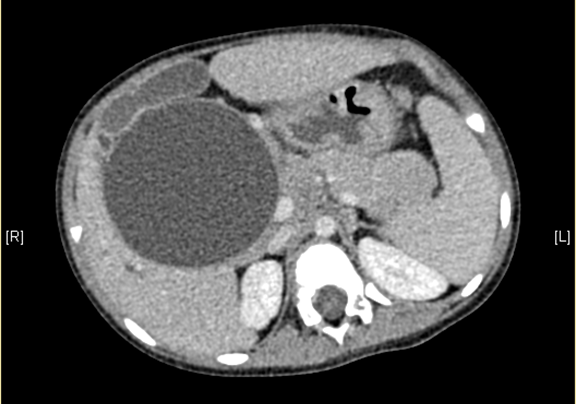

术前CT检查:

静脉期

上腹部增强CT:考虑先天性胆管扩张症(胆总管明显)。

将0.625mm双源薄层CT资料的静脉期和动脉期Dicom格式文件导入海信CAS系统。

通过调节窗宽窗位调整CT序号,对肝实质,胆囊,胆总管,下腔静脉,肝动脉、门静脉及肝静脉等进行三维重建;系统自动计算肝脏体积。